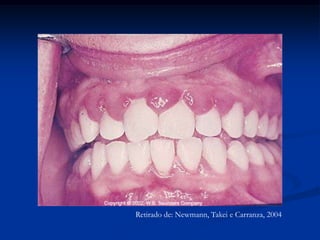

Retirado de: Newmann, Takei e Carranza, 2004

Retirado de: Newmann,Takei e Carranza, 2004